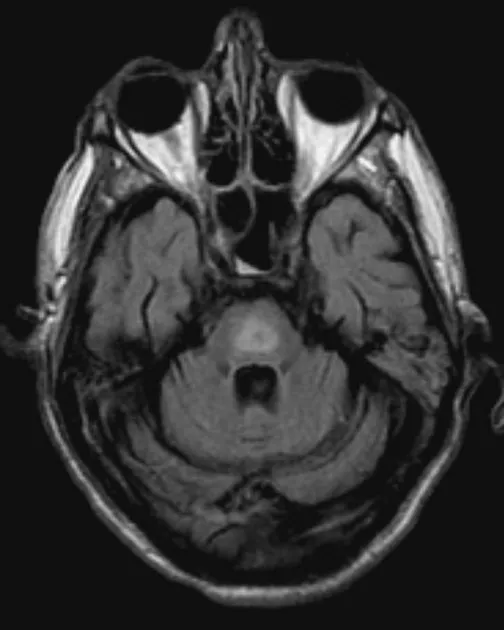

⭐ Rapid correction of chronic hyponatremia can lead to Osmotic Demyelination Syndrome (ODS).